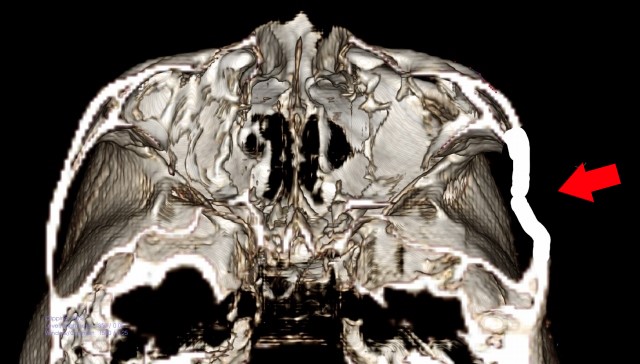

頬骨_痛い時_頬骨の高さの水平線

上のラインで、顔を輪切りにすると。

頬骨_痛い時_頬骨と上顎洞

CT像は、こうなります。

頬骨の裏には、

上顎洞という空洞(副鼻腔)があります。

頬骨が痛い事は、

上顎洞炎(副鼻腔炎)と、

関係が近いと言えます。